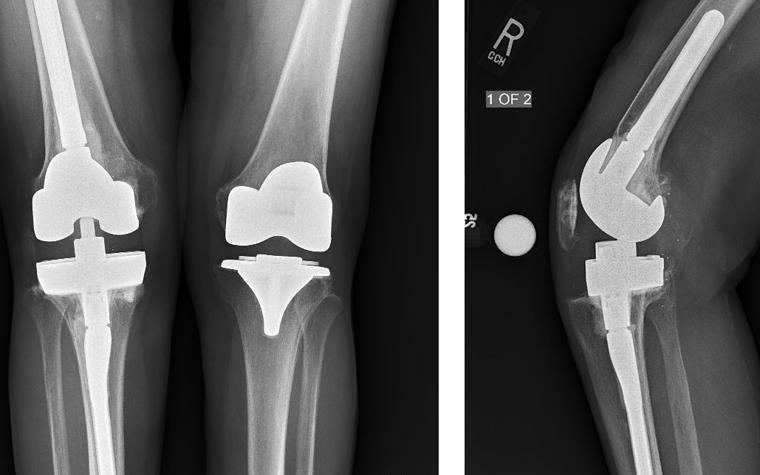

During the templating stage, varying stem sizes are trialed to ensure bony defects will be bypassed by at least two cortical diameters.

Planning this case preoperatively with OrthoView enabled Krishna Tripuraneni to identify several key factors easily: the point at which to stop reaming (to avoid an intraoperative fracture), suitable stem sizes (diameter and length), as well as additional component sizes, the offset requirements for the stem, and the size of stem extension needed to obtain diaphyseal engagement. Digital preoperative planning also made it quick and easy to establish the mechanical alignment of the leg with the use of the SmartKnee Wizard.

Postoperative critiques:

- As there was intraoperative hyperextension, tibial augments and a 17 mm polyethylene were used to balance the extension space (in addition to distal femoral augments), which caused the joint line to be raised by a few millimeters.

- A hybrid cementation technique was used for this case.

- The postoperative ROM at the one-year follow-up was found to be 0-115 degrees.